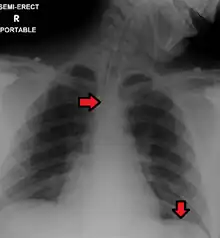

Great care must be taken to ensure that the tube has not passed through the larynx into the trachea and down into the bronchi. The reliable method is to aspirate some fluid from the tube with a syringe. This fluid is then tested with pH paper (note not litmus paper) to determine the acidity of the fluid. If the pH is 4 or below then the tube is in the correct position. If this is not possible then correct verification of tube position is obtained with an X-ray of the chest/abdomen. This is the most reliable means of ensuring proper placement of an NG tube.[10] The use of a chest x-ray to confirm position is the expected standard in the UK, with Dr/ physician review and confirmation. Future techniques may include measuring the concentration of enzymes such as trypsin, pepsin, and bilirubin to confirm the correct placement of the NG tube. As enzyme testing becomes more practical, allowing measurements to be taken quickly and cheaply at the bedside, this technique may be used in combination with pH testing as an effective, less harmful replacement of X-ray confirmation.[11] If the tube is to remain in place then a tube position check is recommended before each feed and at least once per day.

Complications with nasogastric intubation can occur due to incorrect initial placement of the nasogastric tube or due to changes in tube position that go unrecognized. Nasogastric tubes mistakenly placed in the trachea or lungs can lead to aspiration of enteral feeds or medications administered through the NG tube. This can also lead to pneumothorax or pleural effusion, which often requires a chest tube to drain.[14][4] Nasogastric tubes can also be mistakenly placed within the intracranial space; this is more likely to occur in patient who already have specific types of skull fractures.[4]